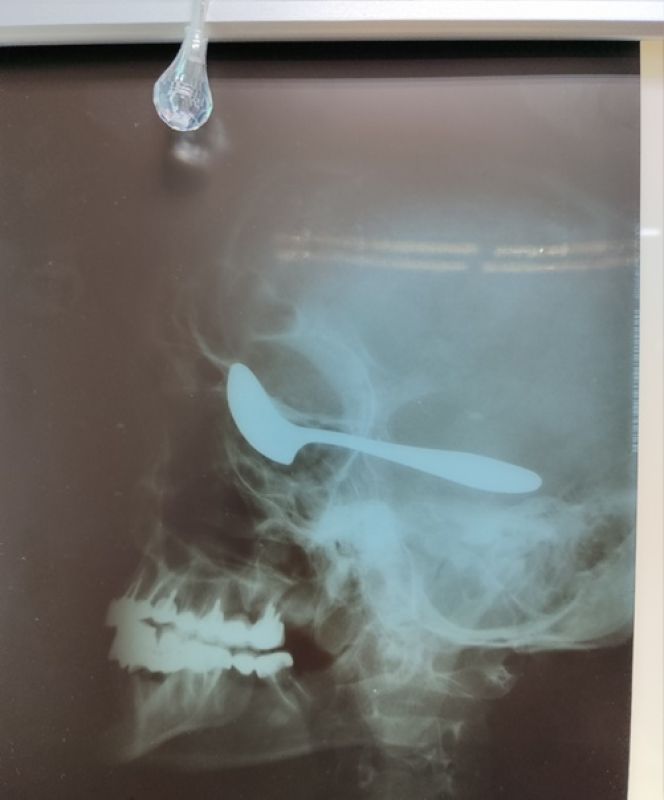

Мужчина в приступе белой горячки целиком вогнал ложку себе в глаз в больнице Алатырского района Чувашской Республики, сообщило учреждение вчера, 13 февраля.

Мужчина поступил в больницу с обострением панкреатита после продолжительного запоя. Внезапно он стал вести себя неадекватно: набросился на соседа, а потом схватил ложку и вонзил её себе в голову через глаз.

Врачи быстро подоспели на помощь мужчине: ему сделали все необходимые анализы, после чего извлекли инородный предмет. Зрение чудом удалось сохранить, однако пациент оказался частично парализован. Его ждёт курс реабилитации.